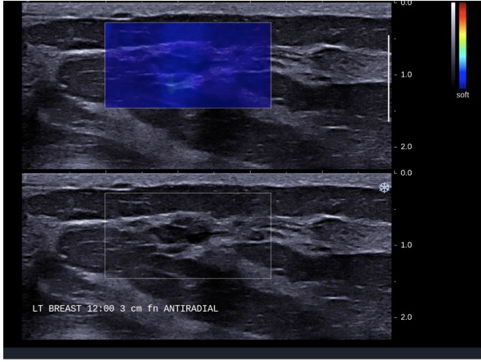

Рисунок 2

Рисунок 3

Рисунки 2 и 3 изображают две различные инфильтрирующие протоковые карциномы демонстрирующие признаки злокачественной эластографии, включая гетерогенную эхотекстуру, неправильную форму и эластограмму жесткого цвета, которая выглядит больше, чем изображение в оттенках серого (стандартное УЗИ). Цветовая гамма является мерой жесткости. На этих изображениях красный указывает на очень жесткую ткань, зеленый/желтый указывает на промежуточную жесткость, а синий указывает на низкую жесткость.

Рисунок 4

Рисунок 5

На Рисунках 4 (кластерная микроциста) и 5 (фиброаденома) изображены два доброкачественных очага, демонстрирующих типичные свойства эластографии на сдвиговых волнах: однородная овальная форма и очень мягкая эластограмма, которая также имеет одинаковый размер, как на серой шкале, так и на эластографии на сдвиговых волнах.